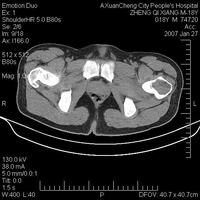

1.X線檢查 通常病變發生於長骨的骨骺內,呈圓形或橢圓形,直徑2~4cm低密度陰影 邊緣清晰,周圍有反應骨形成硬化緣,某些病灶可見點狀鈣化,相對應的骨幹可見連續的骨膜反應(圖1,2) 有時病變可伴有動脈瘤樣骨囊腫,X線片會顯示膨脹。成軟骨細胞瘤的X線表現的特點是在骨骺或骨性突起處有一位於中心或者偏心的溶骨性病變,其大小通常在5~6cm,病變界線清楚呈圓形或卵圓形。腫瘤周圍有一很細的硬化邊緣可將腫瘤與正常組織分開(圖1)。臨近的軟骨可以變薄或受到侵蝕。腫瘤可擴展至軟骨下骨,但很少進入關節間隙 有30%~50%的病例在病變中有鈣化灶。由於鈣化的程度不盡相同,有時需X線斷層或CT的幫助才能確定某些鈣化灶。約有30%的病例在鄰近的骨幹或乾骺端出現骨膜反應。軟組織出現包塊和並發病理性骨折者少見。